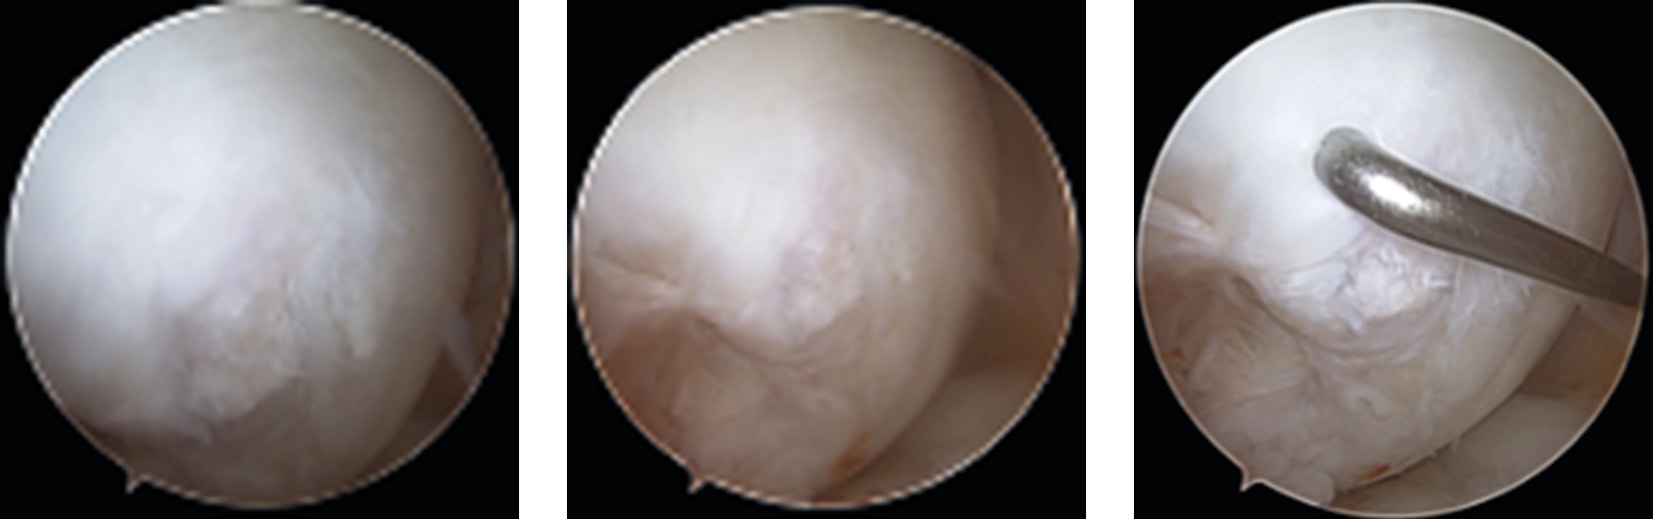

Follow-up evaluation was performed 8 months after the reconstruction. Arthroscopy revealed the site reconstructed with autologous bone and a collagen membrane, covered by coarse fibrous tissue that seemed stable upon probing with a hook (Fig. 3).

Fig. 3. Patient B. Arthroscopic view 8 months after reconstruction.